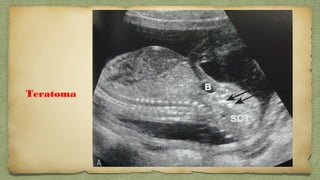

Caudal

regression

Teratoma